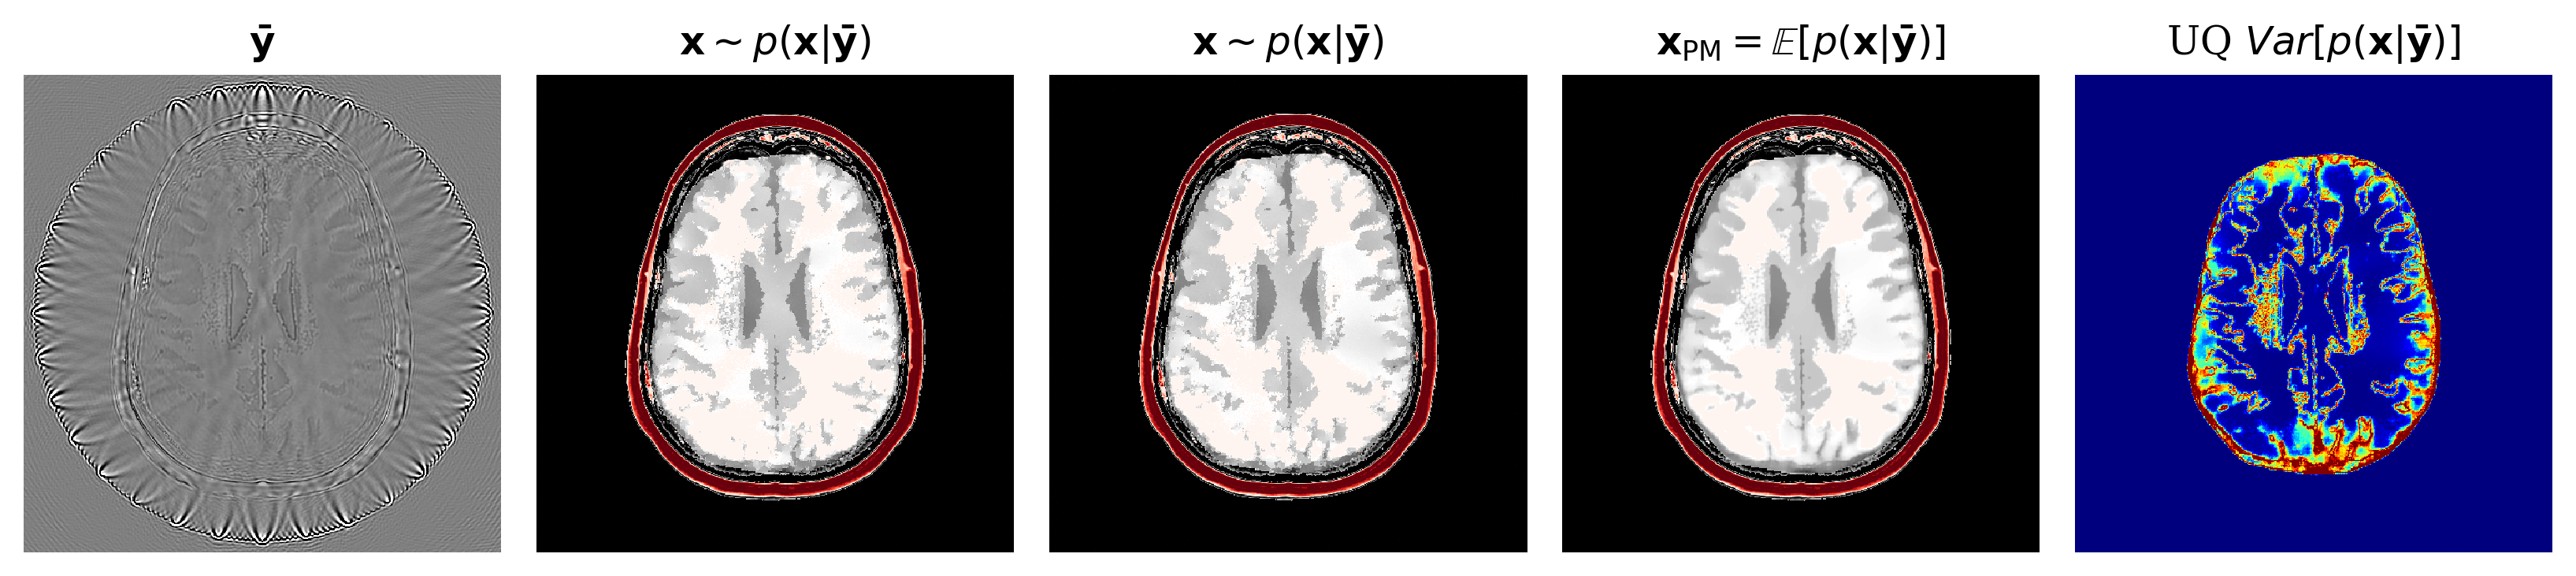

3.2 Image reconstruction from posterior samples

Once trained, our conditional normalizing flow can generate samples from the posterior with Algorithm 2. The computational cost of posterior sampling is dominated by the calculation of the physics-informed summary . This takes second per source and seconds in total for all sources (on 4 core Intel Skylake CPU). This calculation only needs to be done once per ultrasound experiment after which many posterior samples can be generated each at the cheap cost of one inverse network evaluation (20ms/sample). With these posterior samples, statistical point estimates can be calculated including the minimum mean squared error (MMSE) estimator given by the posterior/conditional mean that serves as our image reconstruction. For UQ, we look at the intra-sample variation between posterior samples. To visualize UQ on the entire image reconstruction we use the posterior variance . The posterior mean (and variance) is calculated by approximating their expectations with an average over posterior samples

See Appendix 4.7 for an analysis of the quality of as the number of posterior samples increases. In this work, we concentrate on the posterior mean because it is the estimator with minimal mean squared error Whang et al. (2021). Figure LABEL:fig:basic contains an example of the input and output of the proposed image reconstruction algorithm including UQ.

fig:basic